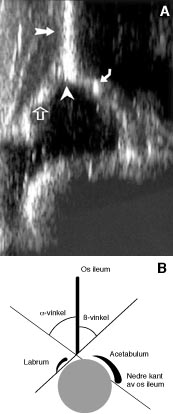

Ultralydundersøkelsen ble som regel foretatt før utskrivning fra barselavdelingen (5. dag), men noen få barn ble undersøkt senere. Barna ble undersøkt etter en modifisert Grafs metode (1) i sideleie i en stabiliserende form med 7,5 mHz lineær ultralydprobe (B&K Medical Systems 3535). To avbildninger ble tatt av hver hofte, og inklinasjonsvinkelen av acetabulum ( α -vinkelen) ble målt på bildene (fig 1). Vi vurderte også formen på acetabulums lateralhjørne og testet stabiliteten i hoftene under ultralydundersøkelsen med en provokasjonsmanøver tilsvarende Barlows test.

Grafs klassifikasjon av hoftene ut fra ultralydfunnene (1) er svært detaljert. Vi valgte å forenkle den, og inndelte hoftene som vist i tabell 2. β -vinkelen, som angir stillingen av caput femoris i forhold til acetabulum (fig 1), inngår bare i Grafs type 1b, D og 4. Siden vi bare brukte type 4 i vår inndeling, målte vi ikke β -vinkelen rutinemessig. Behandlingsopplegget vårt var likevel tilnærmet det samme som Grafs.

Klassifisering av hofter ved ultralydundersøkelse, modifisert etter Graf (1). Se også figur 1

Type

Definisjon

1

Normal: α -vinkel 60˚, skarpt lateralhjørne i acetabulum, stabil

2a

Umoden hofte: α -vinkel 50 – 59˚, avrundet lateralhjørne, stabil

2c

Hoftedysplasi: α -vinkel 43 – 49˚, defekt lateralhjørne, stabil eller lukserbar

3

Hofteluksasjon: α -vinkel< 43˚, defekt lateralhjørne, lukserbar eller luksert, men reponerbar

4

Hofteluksasjon: α -vinkel< 43˚, luksert hofte, ikke reponerbar